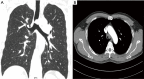

Figure 1

Chest computed tomography (CT) showed a nodule measuring about 1.7 cm × 1.4 cm located at the lower trachea, 1 cm away from the carina.

Figure 14

The computed tomography (CT) reconstructed image of the trachea and the main bronchus on the 12th day postoperative.